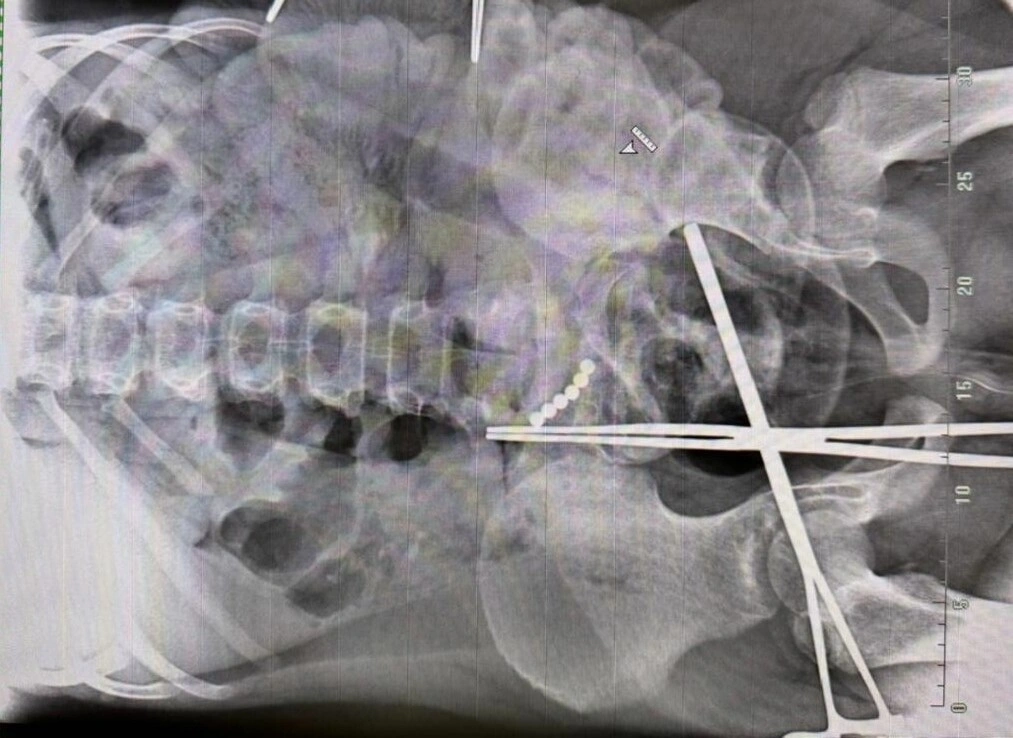

Экстренную операцию провели для 10-летнего мальчика, который проглотил 19 магнитных шариков. Об этом рассказали в областной детской клинической больнице.

Ребёнок проходил с опасными предметами в животе целый месяц, пока не развился перитонит. После этого попал в реанимацию. Хирурги обнаружили множество межкишечных свищей, их разобщили и ушили. Кроме того, начинали операцию с помощью прокола, однако позже пришлось перейти на лапаротомию — открытое вмешательство, когда делается разрез.